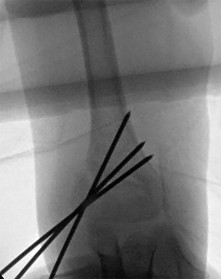

A 7-year-old boy undergoes closed reduction and percutaneous pinning of a displaced supracondylar humerus fracture.

Six hours postoperatively, he is crying uncontrollably on the ward and requires escalating doses of IV opioids. Which of the following is the most reliable early clinical indicator of compartment syndrome in this pediatric patient?